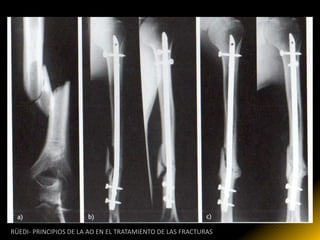

RÜEDI- PRINCIPIOS DE LA AO EN EL TRATAMIENTO DE LAS FRACTURAS